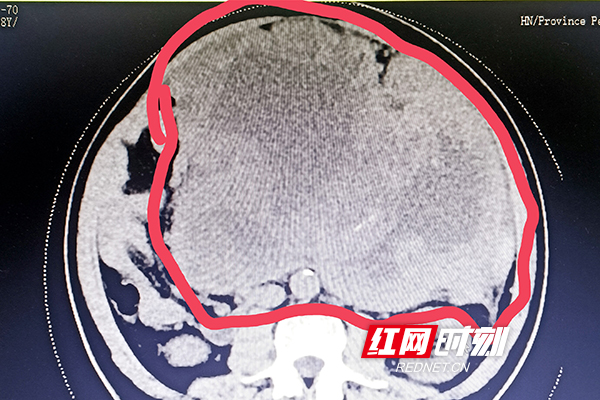

术前影像显示腹腔巨大肿瘤(红圈内)。

红网时刻新闻6月16日讯(通讯员 梁辉 冯玉瑰)长沙58岁的张先生半年前因“痛风”住院,做CT时发现腹腔肿块,因肿块较小就没当回事,也没做任何处理。之后,肿块逐渐增大,稍微活动就感觉胸闷,在当地医院被诊断为“腹腔巨大肿块”。辗转多家医院治疗,但症状未得到明显改善,经人介绍住进湖南省人民医院肝胆五病区,寻求进一步治疗。

梁路峰主任医师团队分析认为,患者腹部肿块为“胃间质瘤”的可能性大,巨大的肿块很可能已经侵犯了相关脏器及重要血管组织,不仅治疗难度大、风险高且容易复发,需多学科联合治疗。肝胆五病区主任汪新天主任医师、梁路峰主任医师立即组织全科讨论及多学科专家会诊,制定了详尽的手术方案。

经过手术团队近3个小时的不懈努力,一个约30×24×14cm大小、重达5.5kg的肿瘤被成功切除,术后病理结果证实为“胃间质瘤”,危险分级为:高度,后续仍需进行基因检测及抗肿瘤治疗。